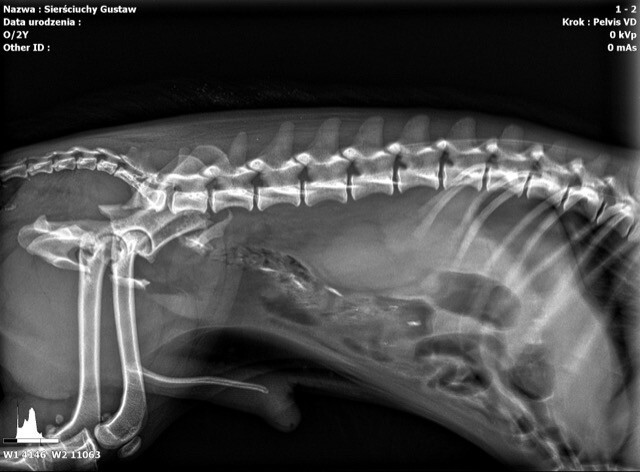

Sam złamałem jednak coś innego... Leżałem pod tujami. I nie to, że nie chciałem wstawać, że byłem zmęczony, że „na kanapie siedzi leń, nic nie robi cały dzień”. Nic z tych rzeczy. Pan psi doktór, tzn. wiecie, ten taki w fartuchu, co zwierzęta leczy, zrobił mi prześwietlenie. Mówię wam, to była przygoda. Czułem się jak prawdziwy gwiazdor, psi celebryta. Jeszcze mi zdjęcia robili...

Okazało się, że mam złamaną miednicę. No, nie powiem, nic przyjemnego. Dostałem leki, miałem operację i dobrze mi poszło. Pomocną łapę podało mi Stowarzyszenie Przytul Sierściucha z Myślenic. Co dalej? Usłyszałem niesamowitą historię o moim koledze. Ten to ma dopiero imię... I do tego złamaną łapę.